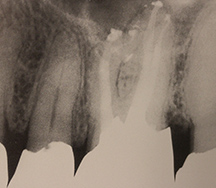

根管充填された症例1

- サーマフィルで3次元的に

根管充填された症例2

根管充填された症例3

根管充填された症例4